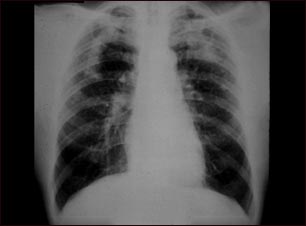

Neumoconiosis complicada del minero

Esta imagen muestra la neumoconiosis complicada del minero. A ambos lados del pulmón hay áreas difusas, pequeñas (de 3 a 5 mm.) y claras. Hay áreas claras grandes junto a los bordes poco definidos en la parte superior de ambos pulmones. Las enfermedades que pueden explicar estos hallazgos en una radiografía son la neumoconiosis complicada del minero (NCM), silicotuberculosis, tuberculosis diseminada, cáncer metastásico de pulmón y otras enfermedades pulmonares infiltrativas difusas.